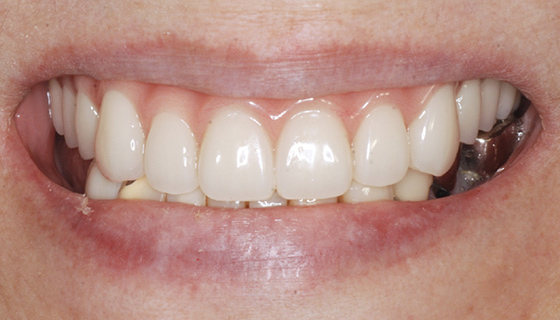

最終補綴物装着

治療期間 | 約2年 |

費用 | 上顎 462万円 (税込) |